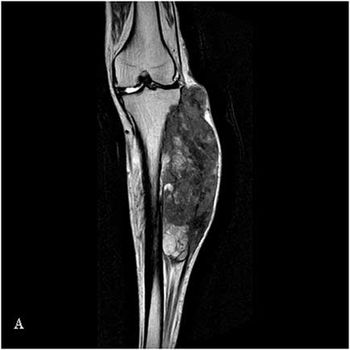

Case History: 45-year-old patient with three-month history of swelling in left leg.